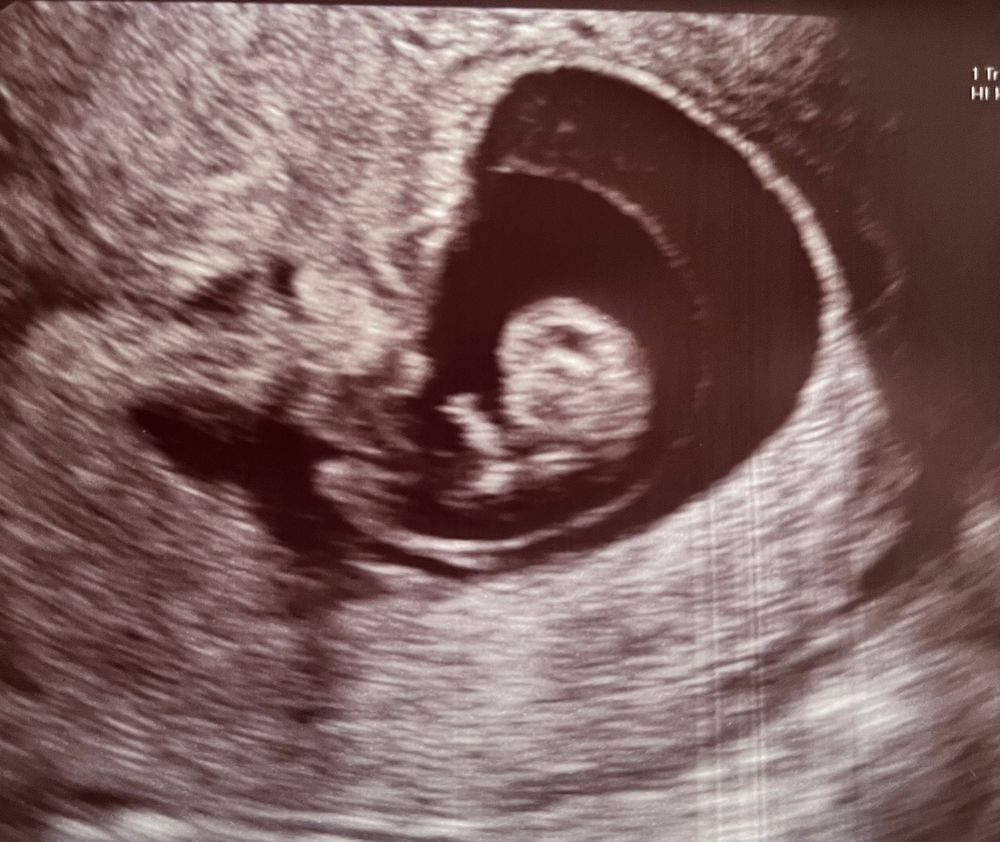

Узи 9 недель и 5 дней

Малыш уже балуется в животике во всю☺️☺️☺️ шевелит ручками и ножками!!! Какое счастье что все хорошо с ним🙏🙏🙏

ктр 29,5 мм (по узи 9 недель и 3 дня ставят),

чсс 176 (опять активничал)